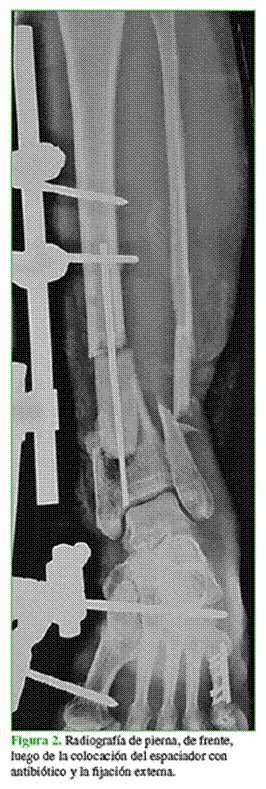

Mujer de 54 años, con una fractura expuesta de tibia distal izquierda Gustillo 3B y pérdida ósea masiva como consecuencia de un accidente de tránsito (Figura 1).

Inicialmente se la trató con limpieza y se le colocó un fijador externo. Limpiezas seriadas (3 en total), colocación de espaciador de cemento con antibiótico (vancomicina-imipenem) (Figura 2) y sistema de aspiración al vacío.